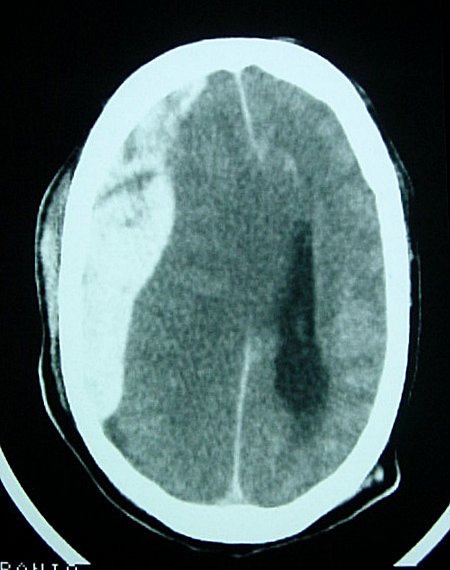

OSCE Pro III 2003 Station 20

1)Describes 2 abnormal findings

2)Diagnosis

3)Name two indication for CT scan

4)Treatment for above condition